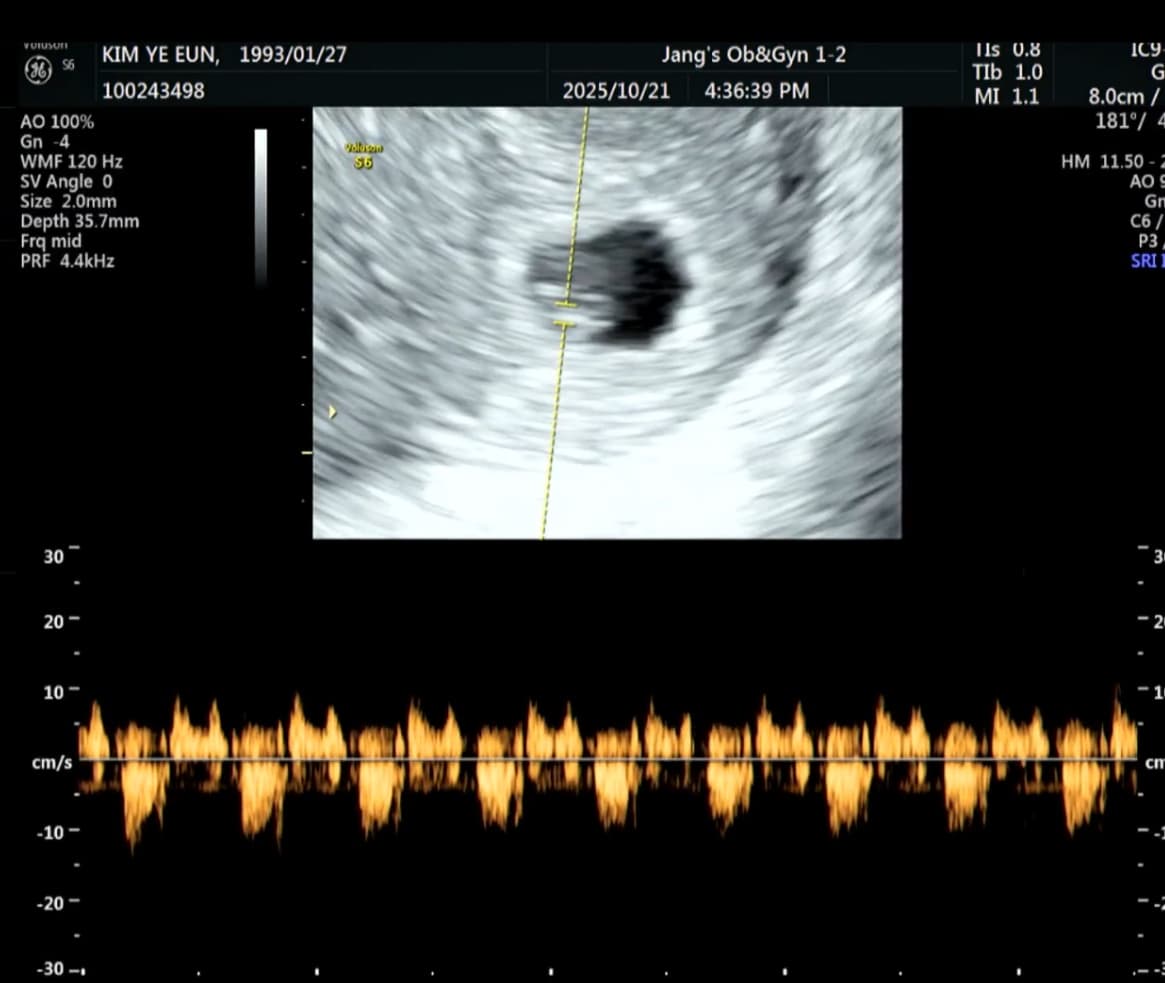

초음파 화면에 작은 점 하나가 보이고.

그 다음 순간,

두근, 두근, 두근.

심장 소리가 들렸다. 0.7cm 밖에 안되는 한 존재가 나에게로 왔다.

그 작은 심장이 이렇게나 힘차게 뛰고 있었다니.

내 안에 심장이 두개가 있다!!🤍